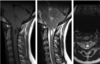

A 14-year-old male presented with months of slowly worsening tingling in his hands. His exam was

intact. Diagnostic work-up included an MRI of the cervical and thoracic spine (figure). What is the most

likely diagnosis?

Hemangiopericytoma

Ependymoma

Neuroblastoma

Astrocytoma

Neurofibroma

A